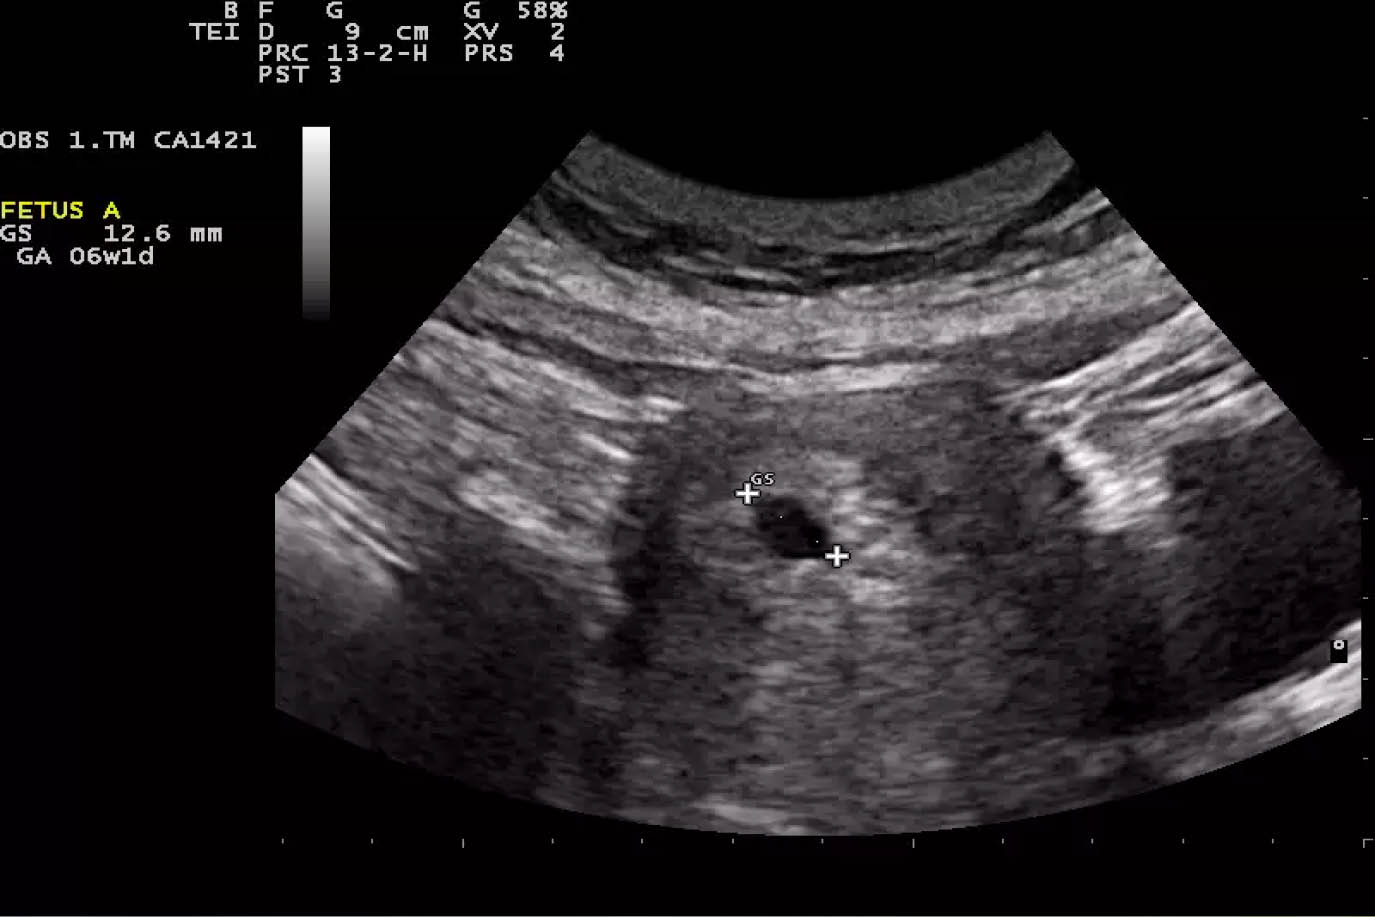

Aplicaciones en obstetricia y ginecología:.

que es una ultrasonografia La ultrasonografía eus ofrece una imagen. La denominación ecografía o ultrasonido se refiere a un procedimiento que emplea ondas sonoras de alta frecuencia para ver el interior del cuerpo, colocando un transductor o. Una ecografía, también conocida como sonograma, es una prueba de diagnóstico por imagen que utiliza ondas sonoras (ultrasonido) para crear imágenes de órganos,. La ultrasonografía es un método de diagnóstico por imagen que utiliza un transductor para emitir. Un ultrasonido de la mama es una técnica de imágenes que se utiliza comúnmente para detectar tumores y otras anomalías en los senos. Aplicaciones en obstetricia y ginecología:. El ultrasonido es un examen médico no invasivo que ayuda a los médicos a diagnosticar y tratar condiciones médicas. Descubre qué es un ultrasonido o ecografía y cuáles son sus usos en el cuidado de la salud.

¿Es malo hacerse muchos ultrasonidos durante el embarazo?

Prácticas para un Examen de Ultrasonografía